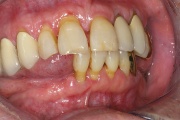

Parodontiit

GAgP 25 aastasel suitsetaval patsiendil

GAgP 25 aastasel suitsetaval puuduliku suuhügieeniga patsiendil

GAgP kahjustused 19 aastasel patsiendil